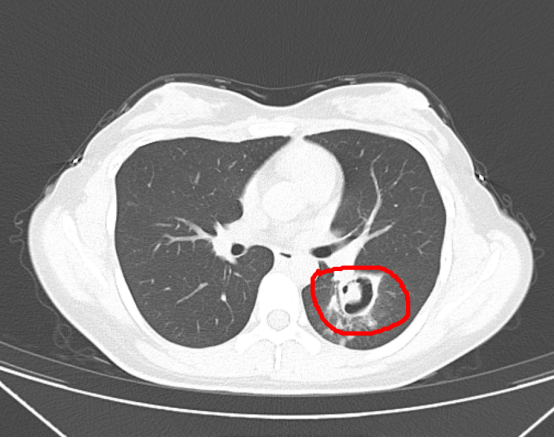

陆主任在仔细分析病情和影像学检查后,高度怀疑朱先生可能合并侵袭性肺曲霉病感染,立即安排行床旁纤维支气管镜检查及肺泡灌洗液查病原体,终于揪出“真凶”——流感相关性肺曲霉病(IAPA),随后立刻针对该患者调整治疗方案,启动抗霉菌治疗。

为了进一步确诊病情,医生为她做了纤维支气管镜检查,发现气道壁上缀着大量白色菌斑,化验后确认是曲霉菌。